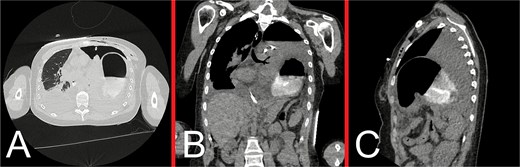

On initial examination, she was haemodynamically stable, with epigastric and left upper quadrant tenderness, but no peritonism. A venous blood gas showed a lactate of 2.7, but no acid–base disturbance or respiratory failure. Chest X-ray (CXR) revealed left hemidiaphragm effacement and a large air-fluid level in the left hemithorax (Fig. 1). A thoracoabdominal computed tomography (CT) scan revealed a markedly dilated stomach displaced into the left hemithorax, suggestive of a large, incarcerated left DH (Fig. 2). A nasogastric tube (NGT) was inserted for immediate gastric decompression (Fig. 1). An emergency gastroscopy confirmed a DH with displacement of the whole stomach into the chest. Endoscopic pyloric cannulation was impossible due to the herniated stomach’s configuration, but there was no mucosal damage, transmural necrosis, or gastric volvulus. Therefore, NGT decompression was continued as a temporizing measure, with planned semi-urgent definitive repair within a few days.

Representative CT images taken during the patient’s initial presentation. (A) Axial, (B) coronal, and (C) sagittal views illustrate a markedly distended stomach with an air-fluid level that is displaced into the left hemithorax, with normal mural enhancement and no evidence of gastric pneumatosis. The left lung is partly collapsed, but there is no evidence of an associated pleural effusion or pneumothorax. The free edge of the ruptured diaphragm is best appreciated on the sagittal view. These findings are consistent with a large, incarcerated left DH, with possible gastric volvulus.